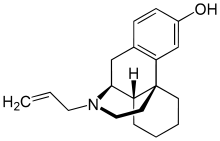

The pharmacodynamic response to an opioid depends upon the receptor to which it binds, its affinity for that receptor, and whether the opioid is an agonist or an antagonist. For example, the supraspinal analgesic properties of the opioid agonist morphine are mediated by activation of the μ1 receptor; respiratory depression and physical dependence by the μ2 receptor; and sedation and spinal analgesia by the κ receptor. Each group of opioid receptors elicits a distinct set of neurological responses, with the receptor subtypes (such as μ1 and μ2 for example) providing even more [measurably] specific responses. Unique to each opioid is its distinct binding affinity to the various classes of opioid receptors (e.g. the μ, κ, and δ opioid receptors are activated at different magnitudes according to the specific receptor binding affinities of the opioid). For example, the opiate alkaloid morphine exhibits high-affinity binding to the μ-opioid receptor, while ketazocine exhibits high affinity to ĸ receptors. It is this combinatorial mechanism that allows for such a wide class of opioids and molecular designs to exist, each with its own unique effect profile. Their individual molecular structure is also responsible for their different duration of action, whereby metabolic breakdown (such as N-dealkylation) is responsible for opioid metabolism.

Several semi-synthetic opioids were developed in Germany in the 1910s. The first, oxymorphone, was synthesized from thebaine, an opioid alkaloid in opium poppies, in 1914.[228] Next, Martin Freund and Edmund Speyer developed oxycodone, also from thebaine, at the University of Frankfurt in 1916.[229] In 1920, hydrocodone was prepared by Carl Mannich and Helene Löwenheim, deriving it from codeine. In 1924, hydromorphone was synthesized by adding hydrogen to morphine. Etorphine was synthesized in 1960, from the oripavine in opium poppy straw. Buprenorphine was discovered in 1972.[228]

Morphinan derivatives

- Butorphanol—agonist/antagonist

- Nalbuphine—agonist/antagonist